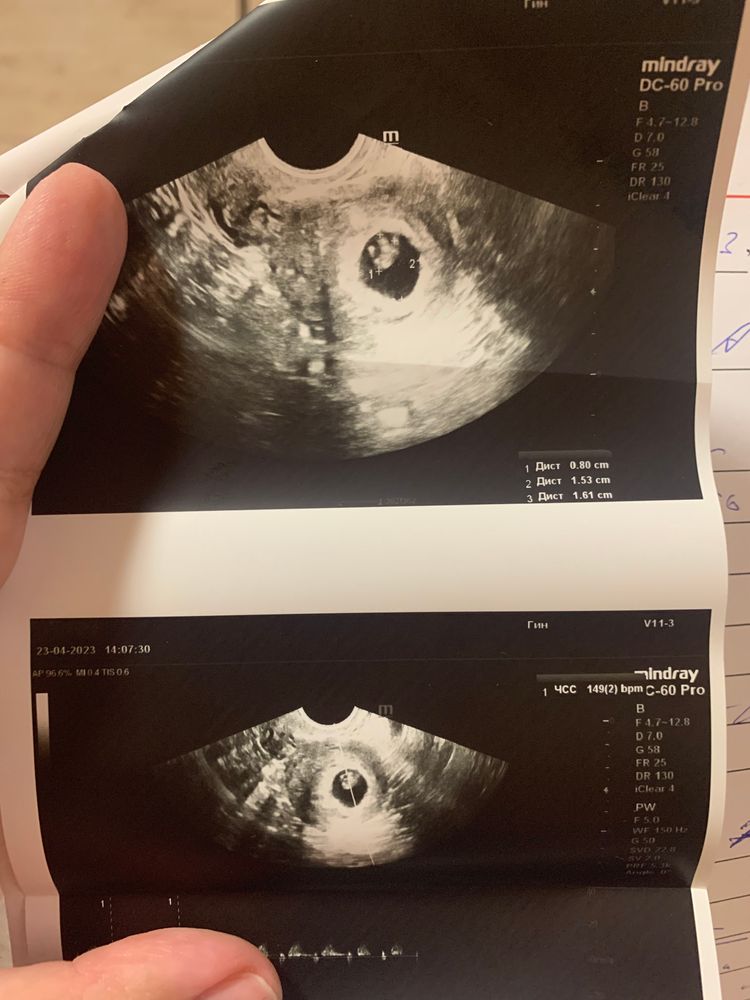

Изображение 7 ровно

Изображение Тут без одного дня 7 недель

Изображение Срок 7 недель, ктр 0.53 см. Соответствует сроку 6 и 2 дня.